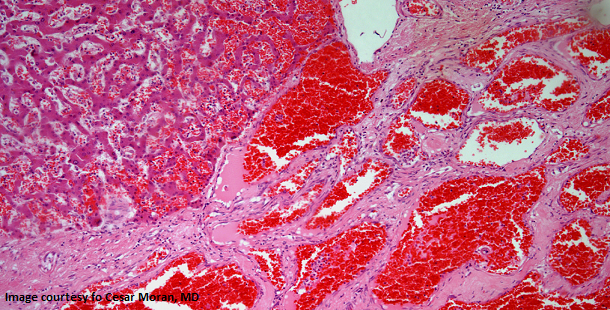

A 38-year-old woman presents with a liver mass. After further evaluation a biopsy is performed. What is your diagnosis?